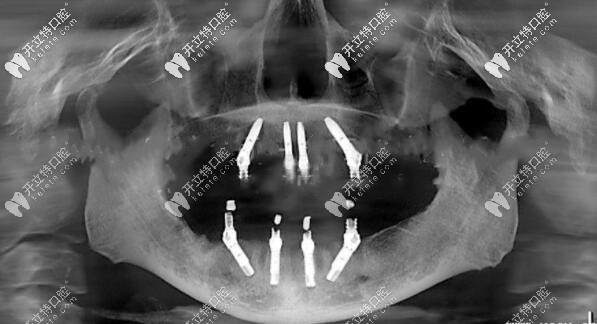

以下是做全口allon4種植牙后拍的CT,可以清晰看出兩顆植體是歪的↓↓↓

全口allon4種植牙后拍的CT